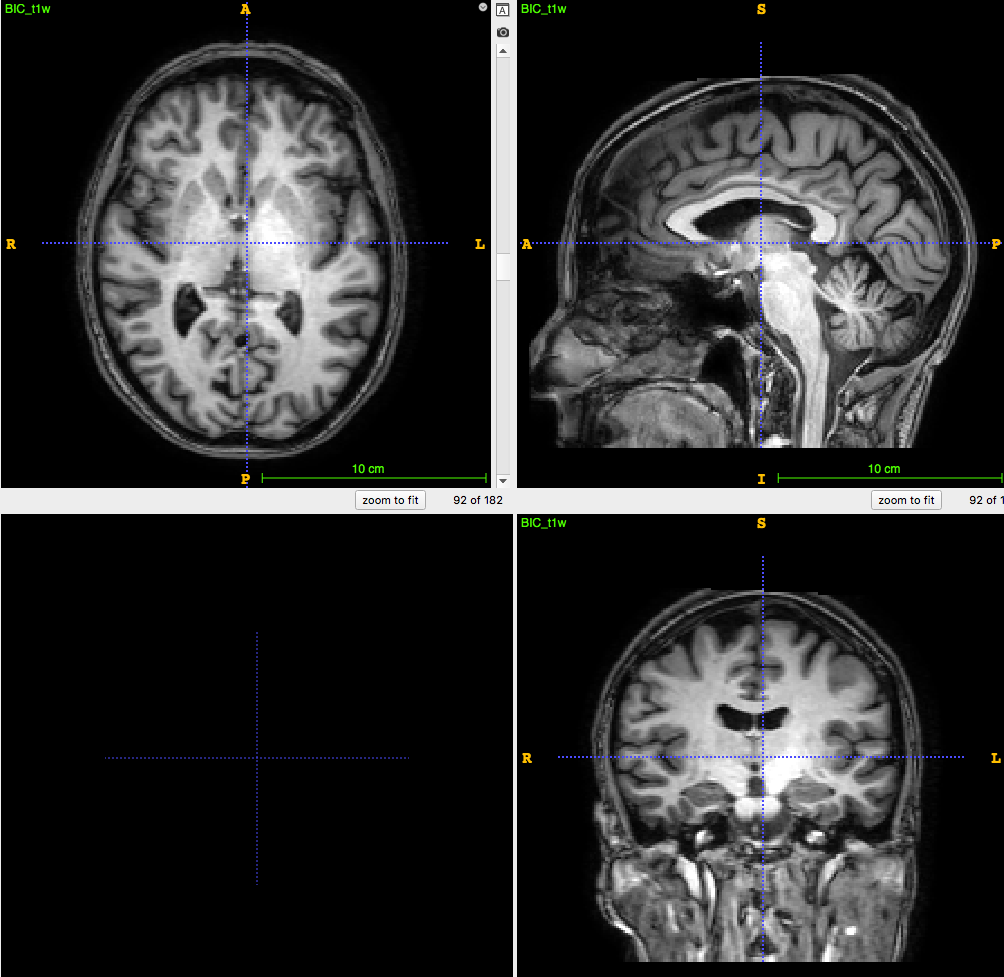

3D T1-weighted MRI:

usually ~1 mm \(^3\) voxel

Segmentation/parcellation at full resolution

PET image:

usually ~8mm \(^3\) voxel

How to apply segmentation?

1. Undersampling T1 segmentation

2. Upsampling PET image